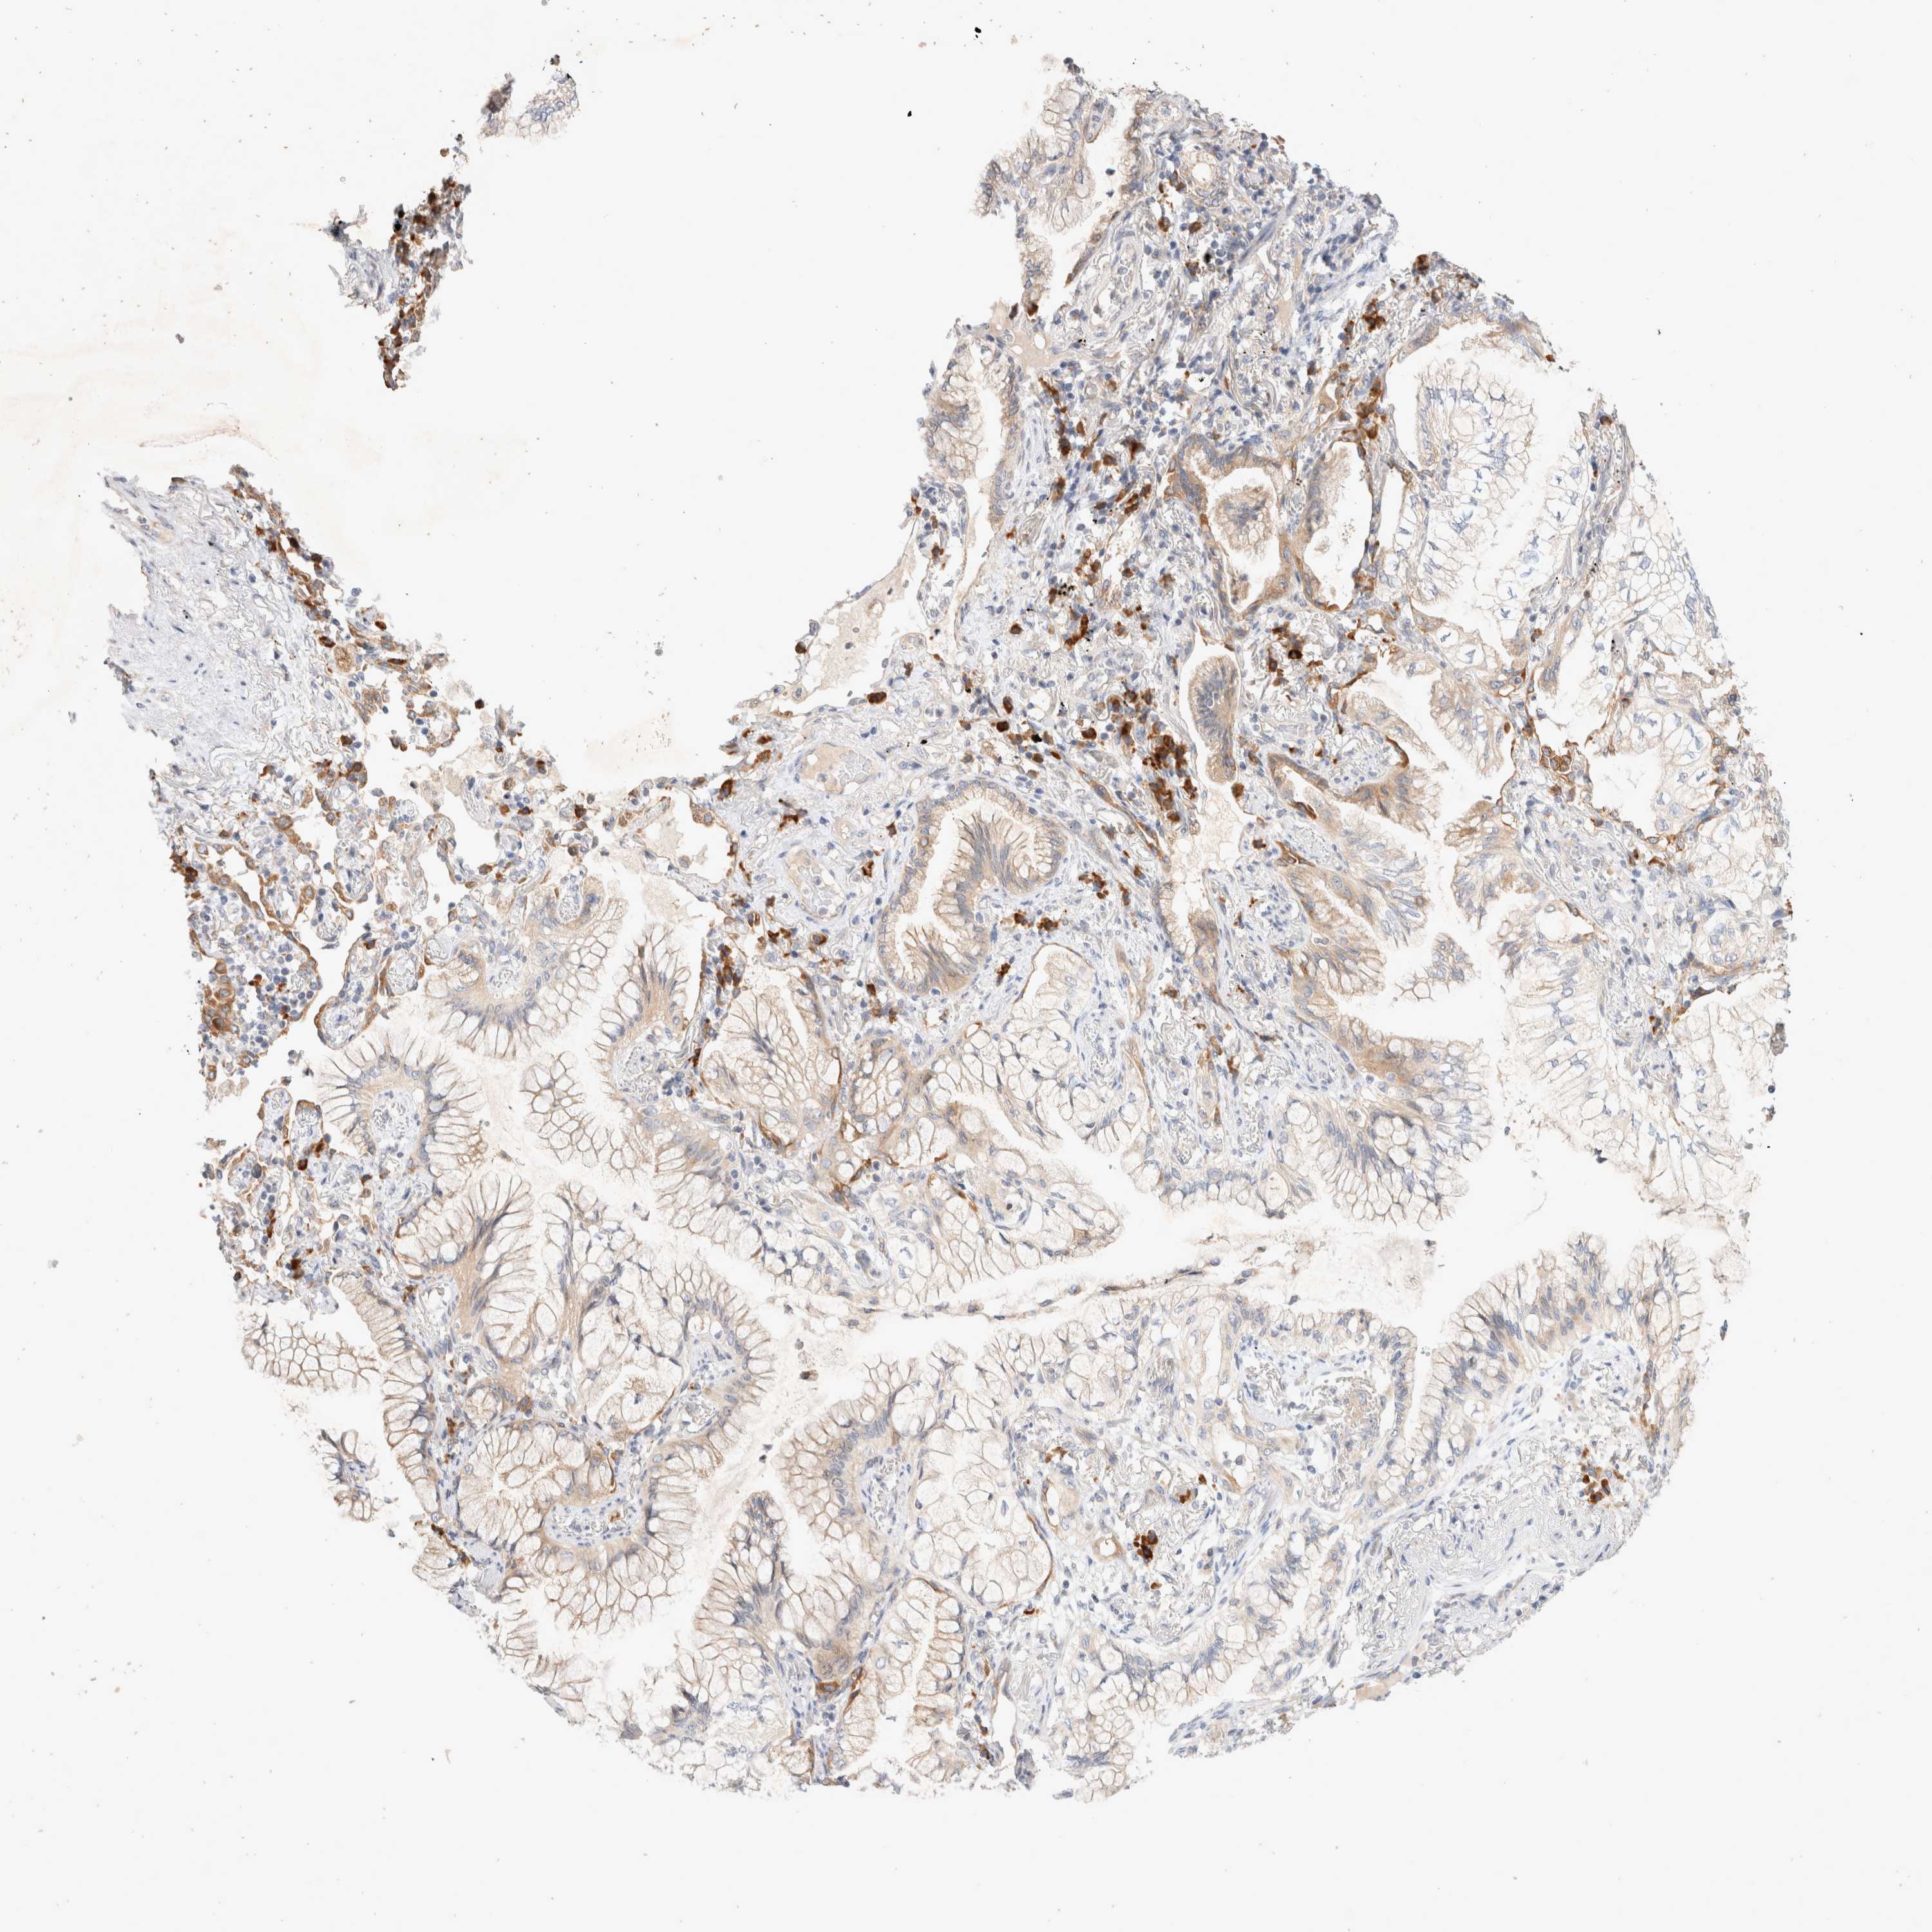

CANCER LUNG CANCER Show tissue menu

NEDD4L is potential prognostic, high expression is favorable in Lung Adenocarcinoma (TCGA)

: 35.56

Average pTPM 47.2

Number of samples 497